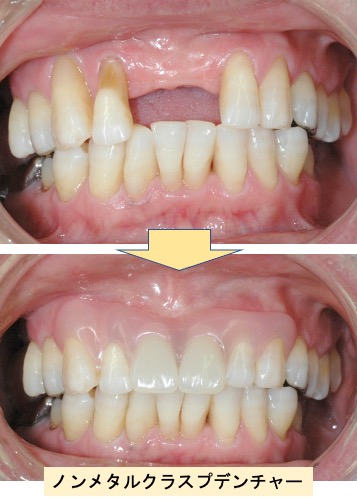

入れ歯(有床義歯)治療

むし歯や歯周病などが原因で、歯を失った場合の治療です。たくさん歯が残っている場合には、ブリッジによる治療が機能性・審美性に優れ、違和感も少ないのですが、ブリッジの支えになる歯が丈夫でなかったり、失った歯の本数が多い場合には入れ歯による治療が適応になります。入れ歯は材質やデザインによって見た目や装着感が大きく異なります。個々の患者さんに合わせた入れ歯を作製いたします。